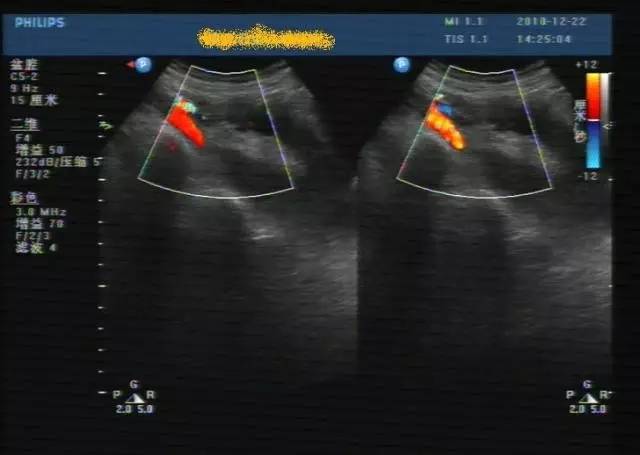

子宫穿孔超声表现图

子宫穿孔超声表现图,子宫穿孔超声图片

超声典型病例子宫穿孔

子宫穿孔的超声诊断

高手进阶:子宫穿孔的超声诊断

子宫穿孔彩超下表现

子宫穿孔彩超图